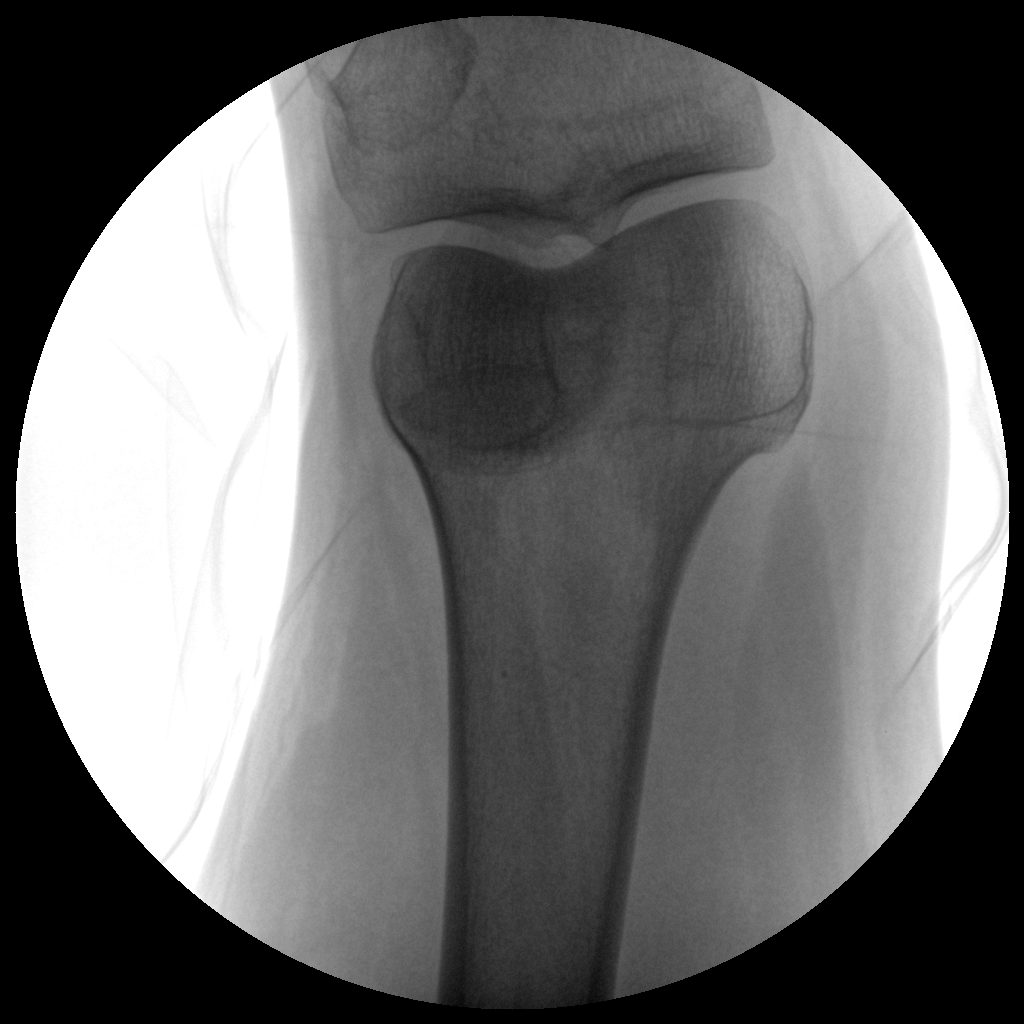

Clinical picture

臨床圖片